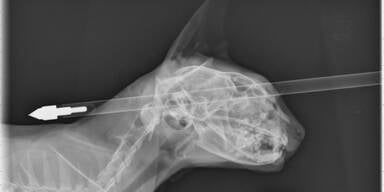

Der Pfeil durchschlug Kater Moo Moos Kopf, doch die Katze überlebte. Ein Unbekannter hatte mit einer Armbrust auf den vier Jahre alten Kater in Neuseeland geschossen. "Er hat sehr, sehr viel Glück gehabt", sagte Tierarzt Jonathan Bray am Mittwoch.

Tierärzte von der Massey-Universität hatten das Tier am Dienstag operiert. Der Pfeil hatte den Schädel des Katers völlig durchdrungen und ragte auf beiden Seiten aus dem Kopf des Tiers. Der Pfeil hatte die Katze oberhalb des Auges getroffen, streifte den Schädelknochen und verfehlte das Gehirn, erklärte Bray. "Die Gehirnmasse wurde nicht beschädigt." Das habe die Operation einfach gemacht. "Es gab eine kleine Verletzung an seiner Nase und seiner Augenhöhle."